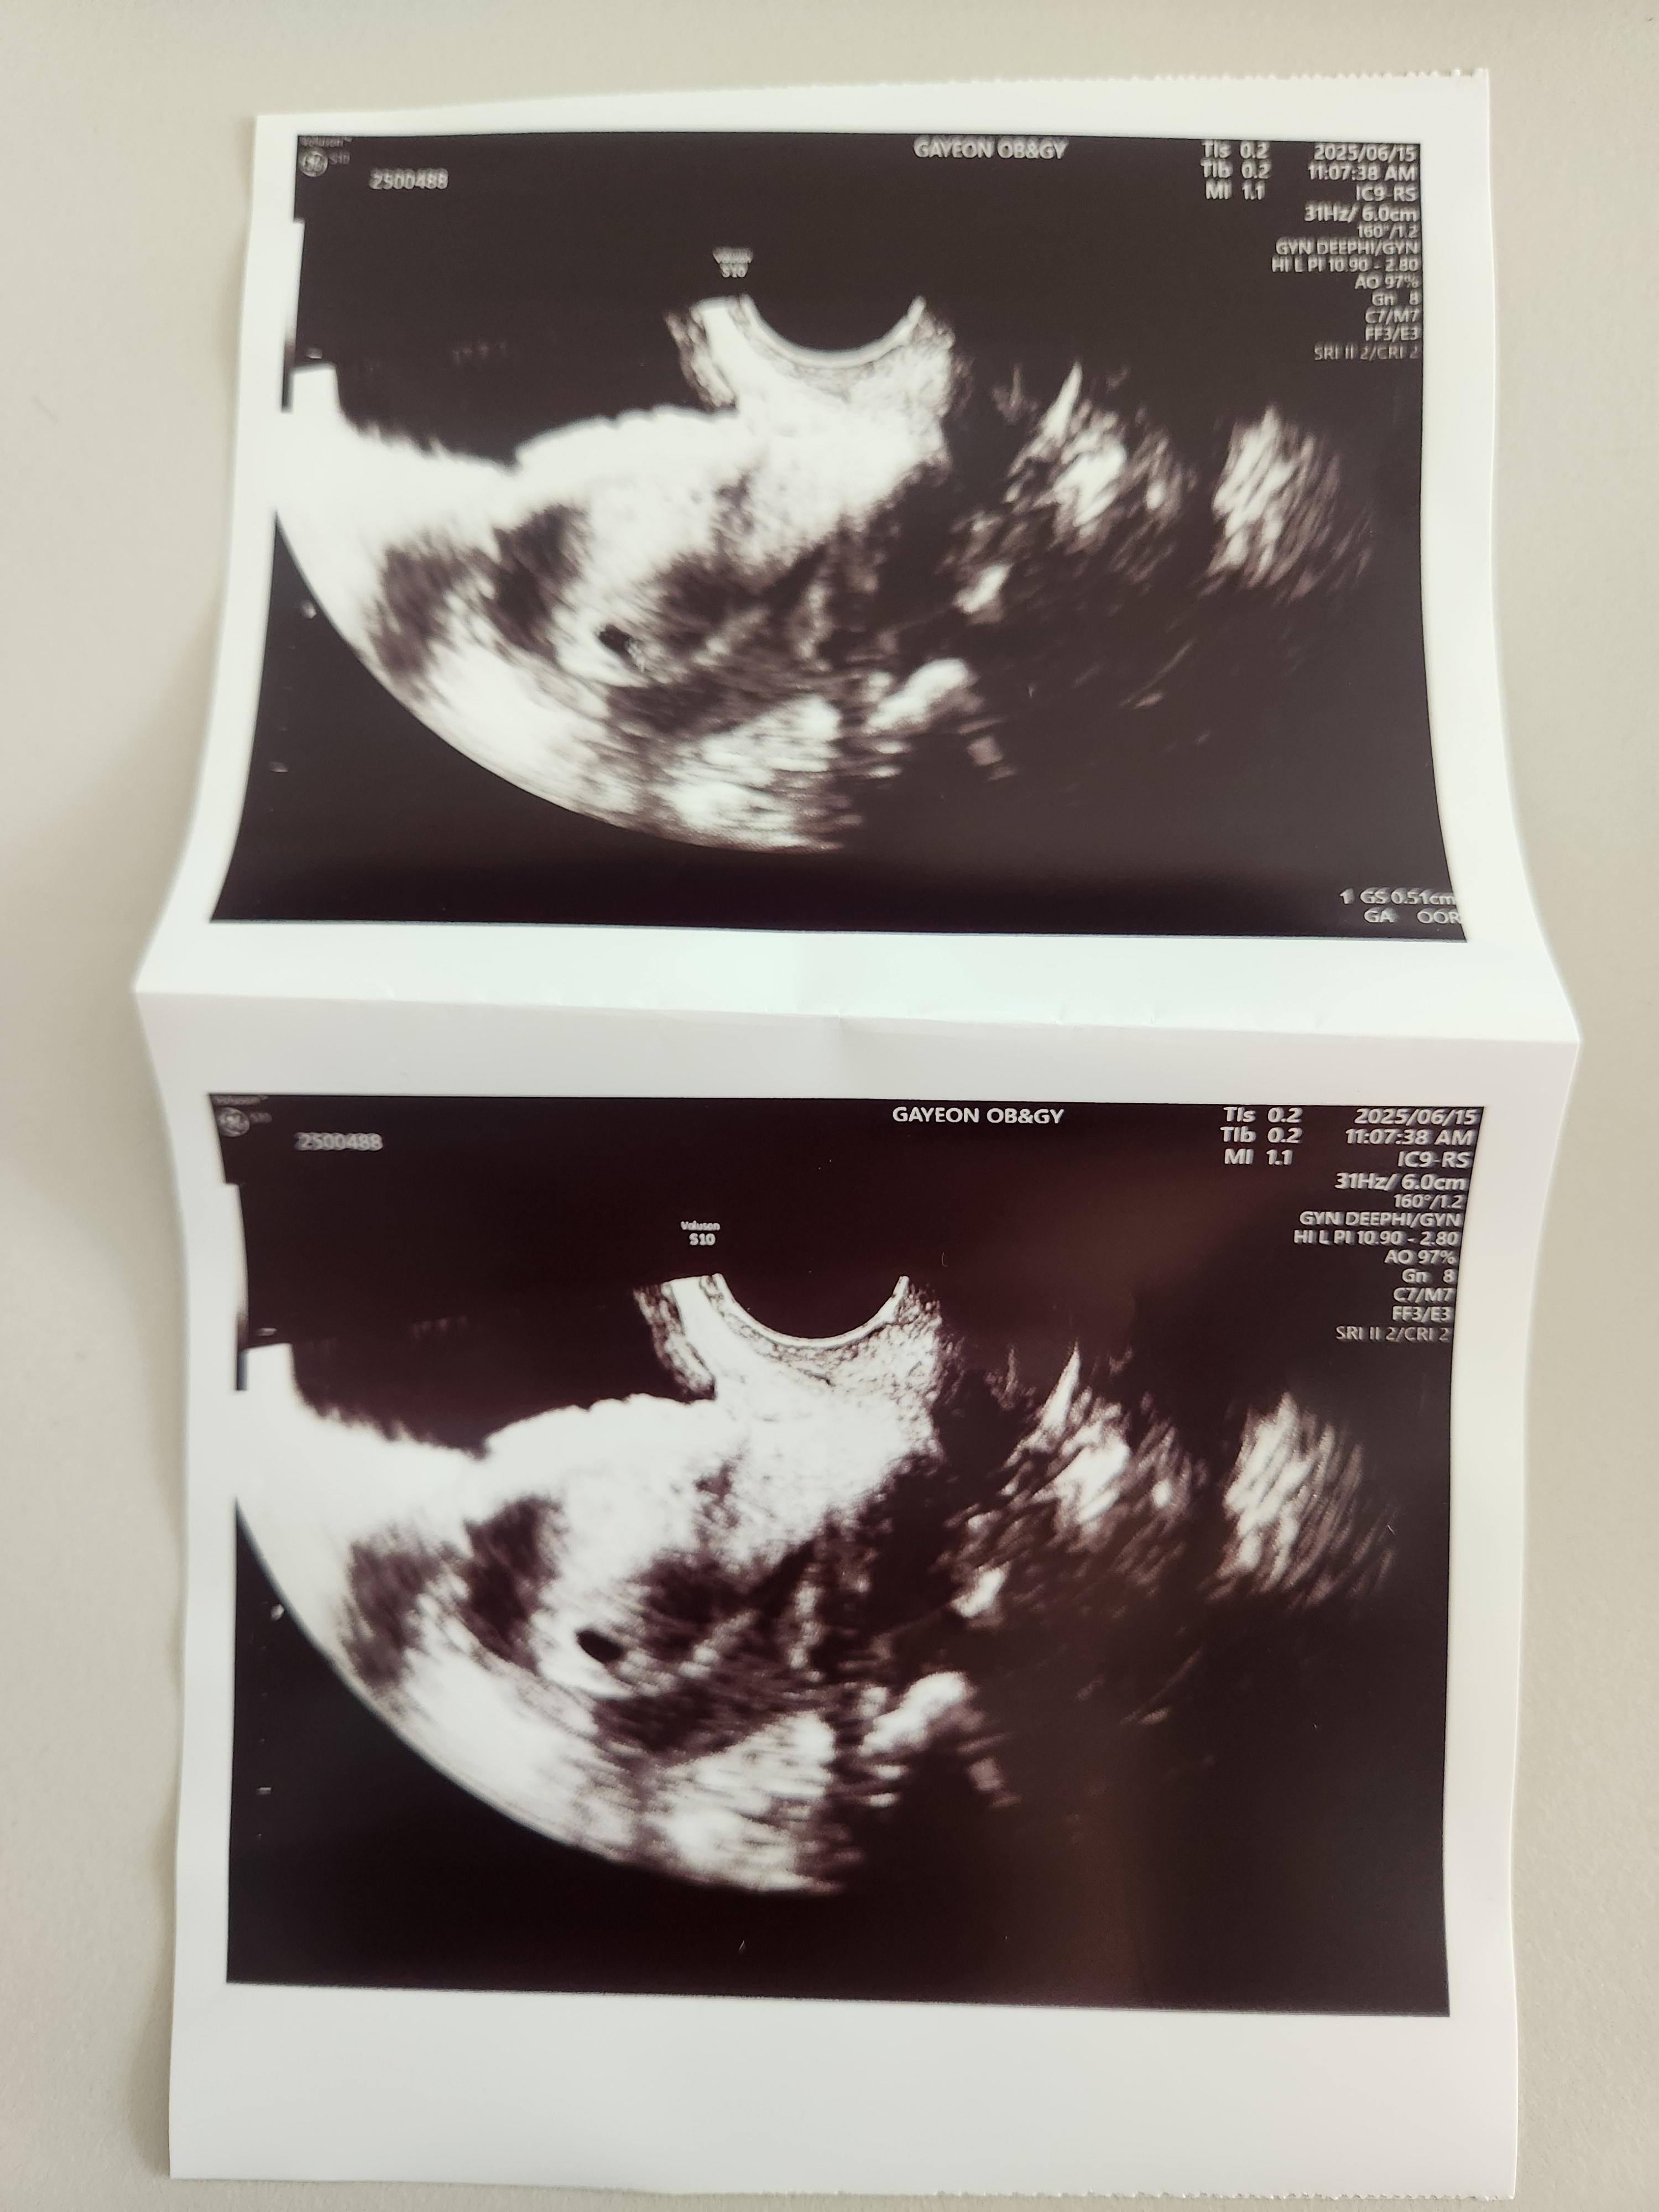

초음파는 질 초음파로 봤고, 아기집을 조그마하게 확인할 수 있었습니다.

아직은 심장소리를 들을 수는 없었고, 주수가 얼마 안돼서 아기집만 볼 수 있었습니다.

일주일 사이에 아기집을 잘 지어놨고, 피고임이나 다른 이상한 것도 없다고 말씀해 주셨습니다.